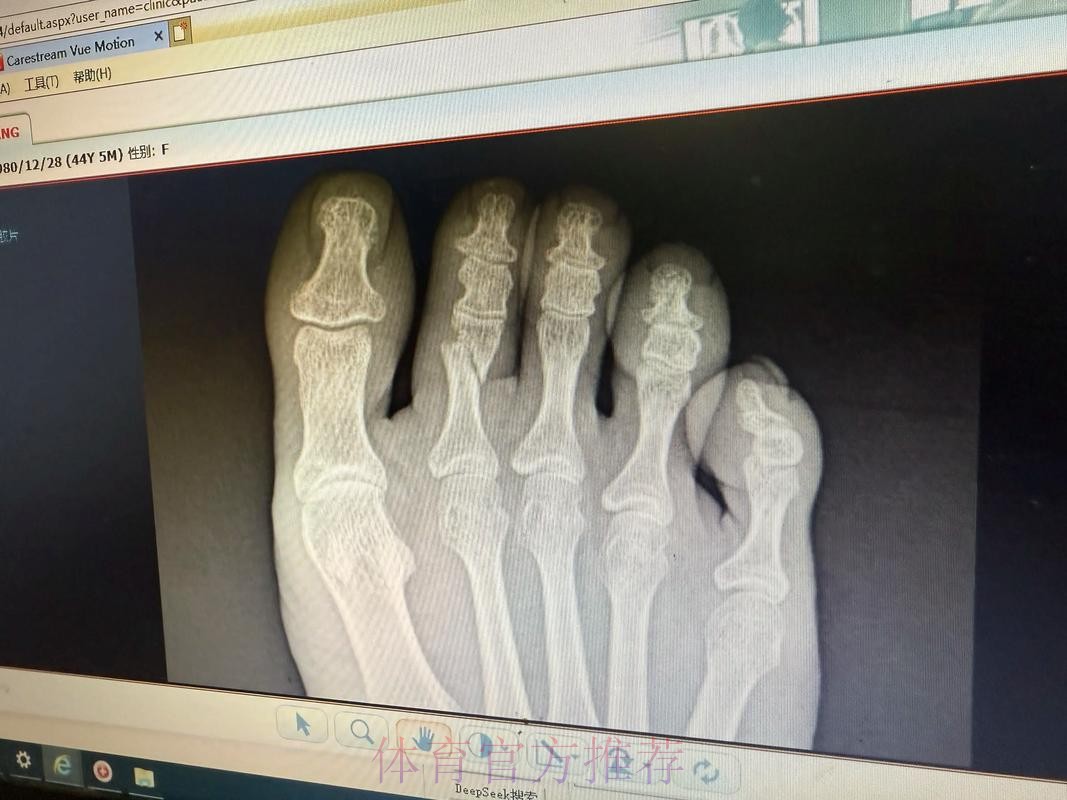

皇马官方-琼阿梅尼左脚第二跖骨不完全应力性骨折

皇马官方伤情通告背后的信号 皇马官方一向在伤病信息上措辞谨慎,但“左脚第二跖骨不完全应力性骨折”这句话本身已经透露出不少关键信息。这是跖骨部位的应力性损伤,而非一次剧烈对抗造成的瞬间骨折,说明问题来自长期负荷积累,是典型的疲劳型伤病。“不完全”意味着骨结构尚未完全断裂,仍保持一定连续性,这对康复时间和方式具有决定性影响。如果处理得当,往往可以通过相对保守的治疗方案避免手术;但一旦急于复出或训练负荷控制不当,就有可能从“不完全”演变为完全性骨折,令缺阵期成倍延长。对于依赖琼阿梅尼在中场完成覆盖和防守平衡的皇家马德里来说,如何在争冠压力下保护好球员、又不让球队竞技水准大幅下滑,将是一场同样艰难的“心理博弈”。

跖骨应力性骨折究竟意味着什么 许多球迷听到“应力性骨折”会下意识以为只是轻微小伤,但在运动医学语境中,这却是对高负荷训练的一种严肃警告。跖骨是足部承重和发力的重要骨骼,足球运动中的短距离爆发、急停变向、频繁起跳落地,都会不断将力量传导至跖骨区域。当训练和比赛的总量超过身体适应阈值,同时恢复时间又不足时,骨组织内部会出现微小裂纹,这些微裂如果得不到及时修复,就逐渐累积形成应力性骨折。不完全应力性骨折通常意味着裂纹尚未贯通骨骼,两侧仍存在结构支撑,因此患者在早期往往还能咬牙坚持训练甚至上场。但正是这种“还能坚持”的错觉,使得应力性骨折在职业足球中极具隐蔽性——当你真正感觉到强烈疼痛时,很可能已经接近完全骨折的边缘。琼阿梅尼的伤情被及时查出,某种程度上说明皇马医疗团队对他的反馈足够重视,也体现了俱乐部在数据监控和身体管理上的专业度。

运动医学视角下的康复和复出节奏 从医学角度看,左脚第二跖骨不完全应力性骨折的康复核心在于“控制负荷”和“逐步恢复”。初期需要通过休息和减压让骨组织完成自我修复,有时会配合使用护靴或拐杖减少足部承重;中期则通过理疗、轻量力量训练和本体感觉训练逐步恢复功能;后期则要加入跑动、变向和带球训练,模拟比赛中的真实对抗场景。真正的难点不在诊断,而在“何时可以回到90分钟高强度比赛”这道关卡。如果皇马在赛程压力或舆论压力下过早安排琼阿梅尼复出,哪怕他在短时间内状态看似良好,也可能埋下复发或二次伤病的隐患。对球员而言,学会倾听身体信号,与医疗团队保持坦诚沟通,避免“硬扛文化”的主导,也是职业生涯能否拉长的重要因素。